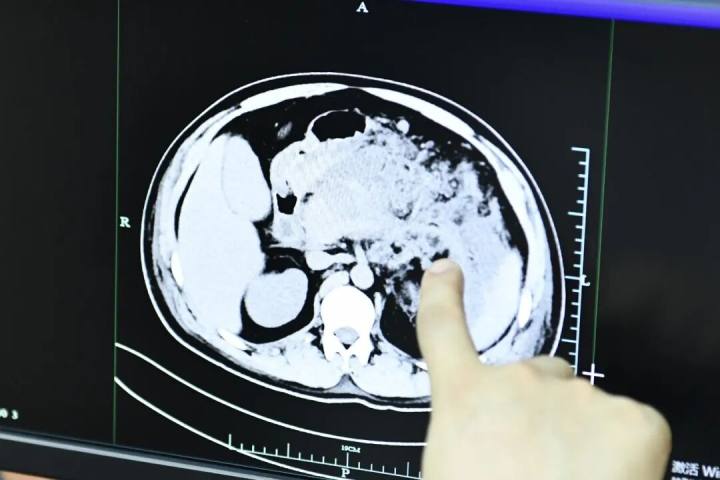

检查结果显示:淀粉酶507U/L,脂肪酶1088U/L,远超正常值。影像显示胰头饱满,伴周围渗出,考虑急性胰腺炎。